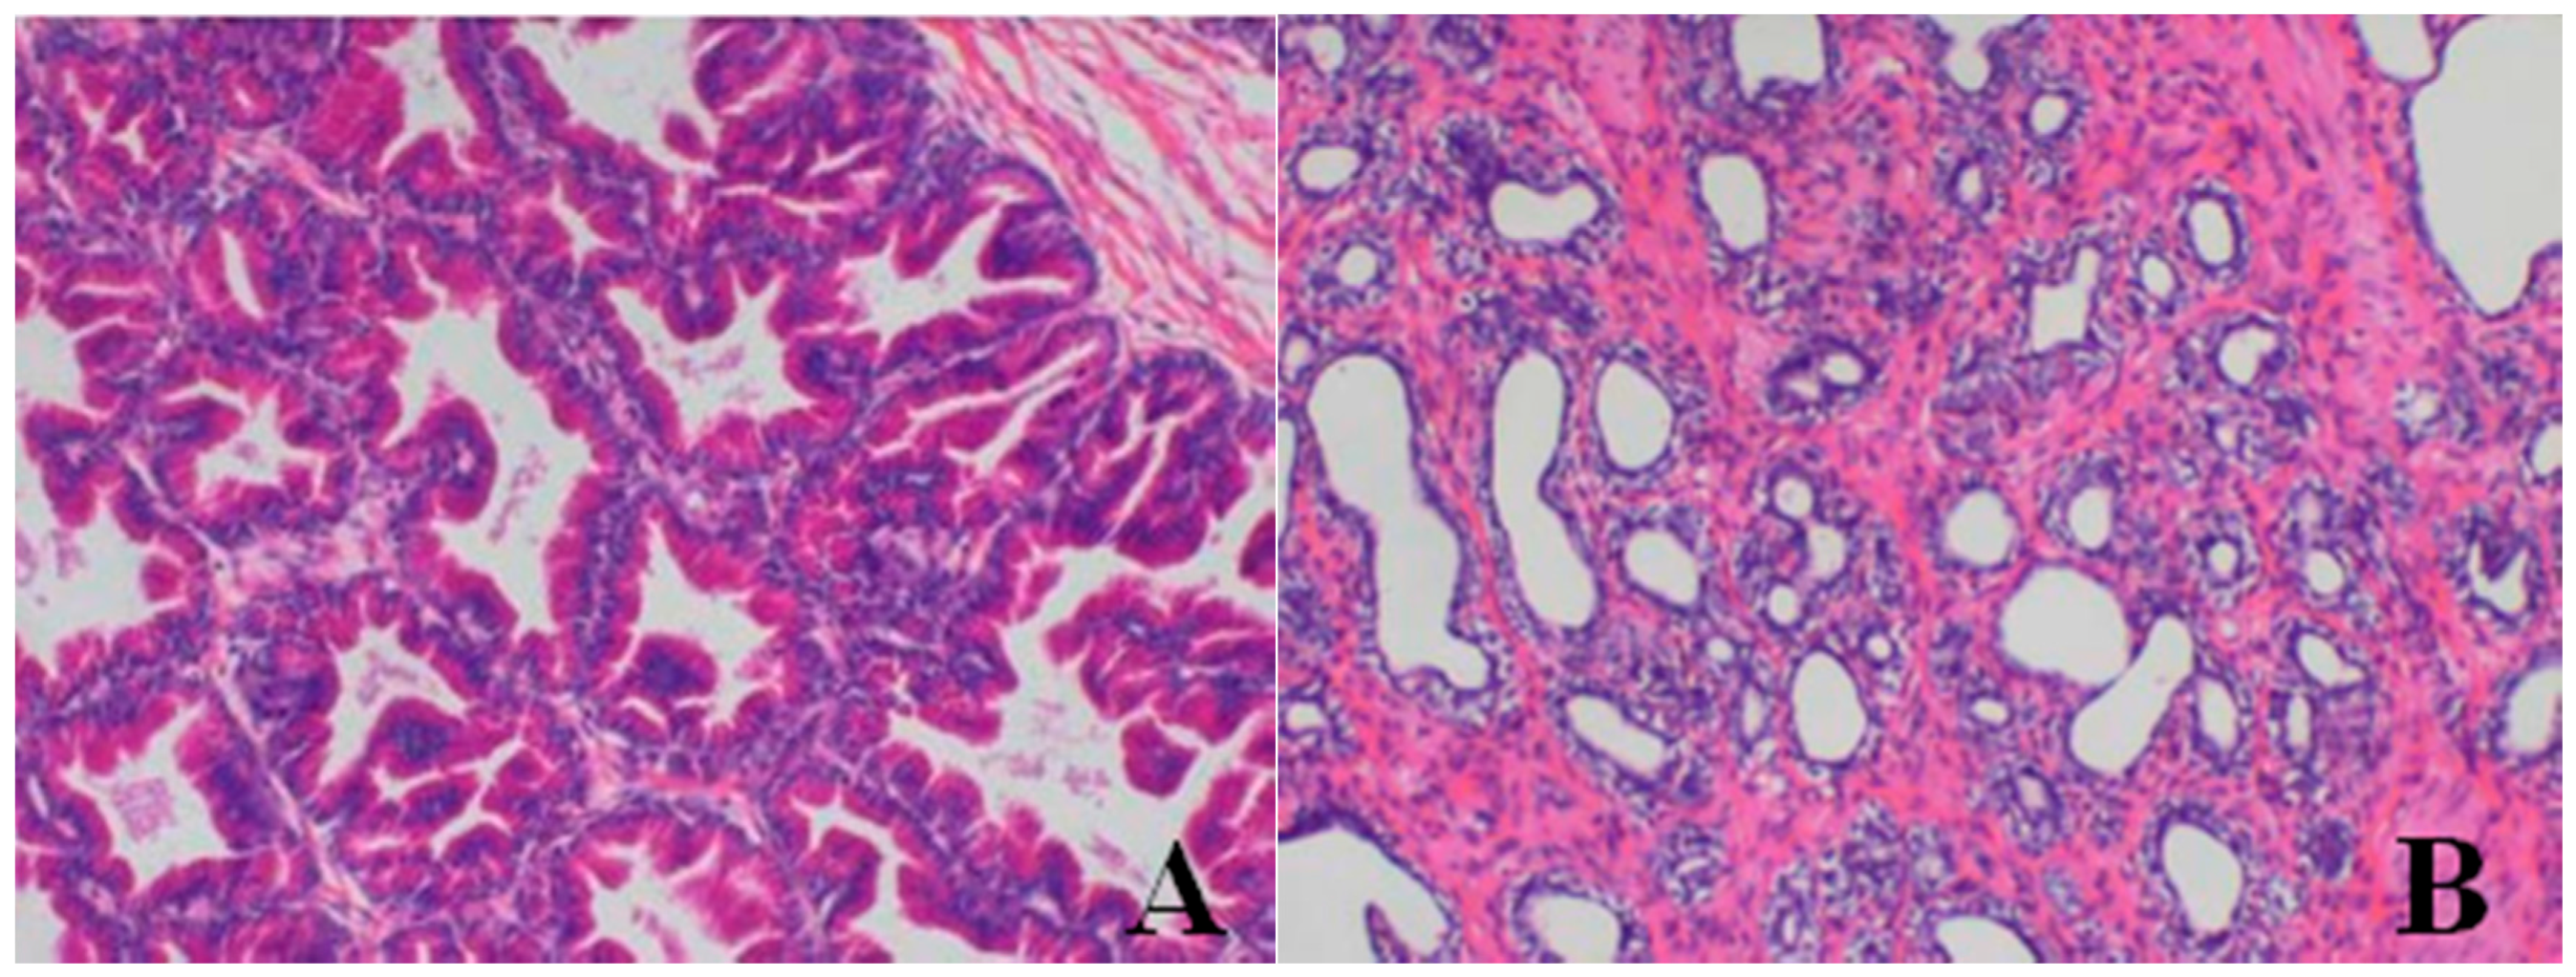

Male reproductive organs (testis, epididymis and prostate)

- Testis: The numbers of seminiferous tubules decreased in dogs belonging to the 80- and 40-mg/kg dose groups, while the tubule lumen decreased and had reduced numbers and types of spermatogenic cells when compared with the control group. Only spermatogonia and some primary and secondary spermatocytes were observed, and there were no mature sperm compared with the control group.

- Epididymis: When compared with the control group, there was a notable lack of mature sperm cells and secretions in the epididymal lumen, as well as a decrease in epididymis lumen size, an irregular shape of the epididymal lumen and an increase in the connective tissue in the interstitium observed in dogs in the 80- and 40-mg/kg dose groups.

- Prostate: When compared with the control group, a reduction in the numbers and size, a thinner epithelium, narrower glandular cavity and increase in the connective tissue in the interstitium were observed in the prostatic acini of dogs in the 80- and 40-mg/kg dose groups.